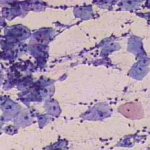

Πινακοθήκη κυτταρολογικών ευρημάτων ΙΙΙ

Οι πινακοθήκες κυτταρολογικών ευρημάτων, έχουν σαν στόχο να εμπλουτίσουν την κυτταρολογική εμπειρία σπουδαστών και ειδικευομένων, όπως ένας άτλαντας.

Παρουησιάζονται λοιπόν τυχαία ευρήματα, από το καθημερινό γυναικολογικό ιατρείο.